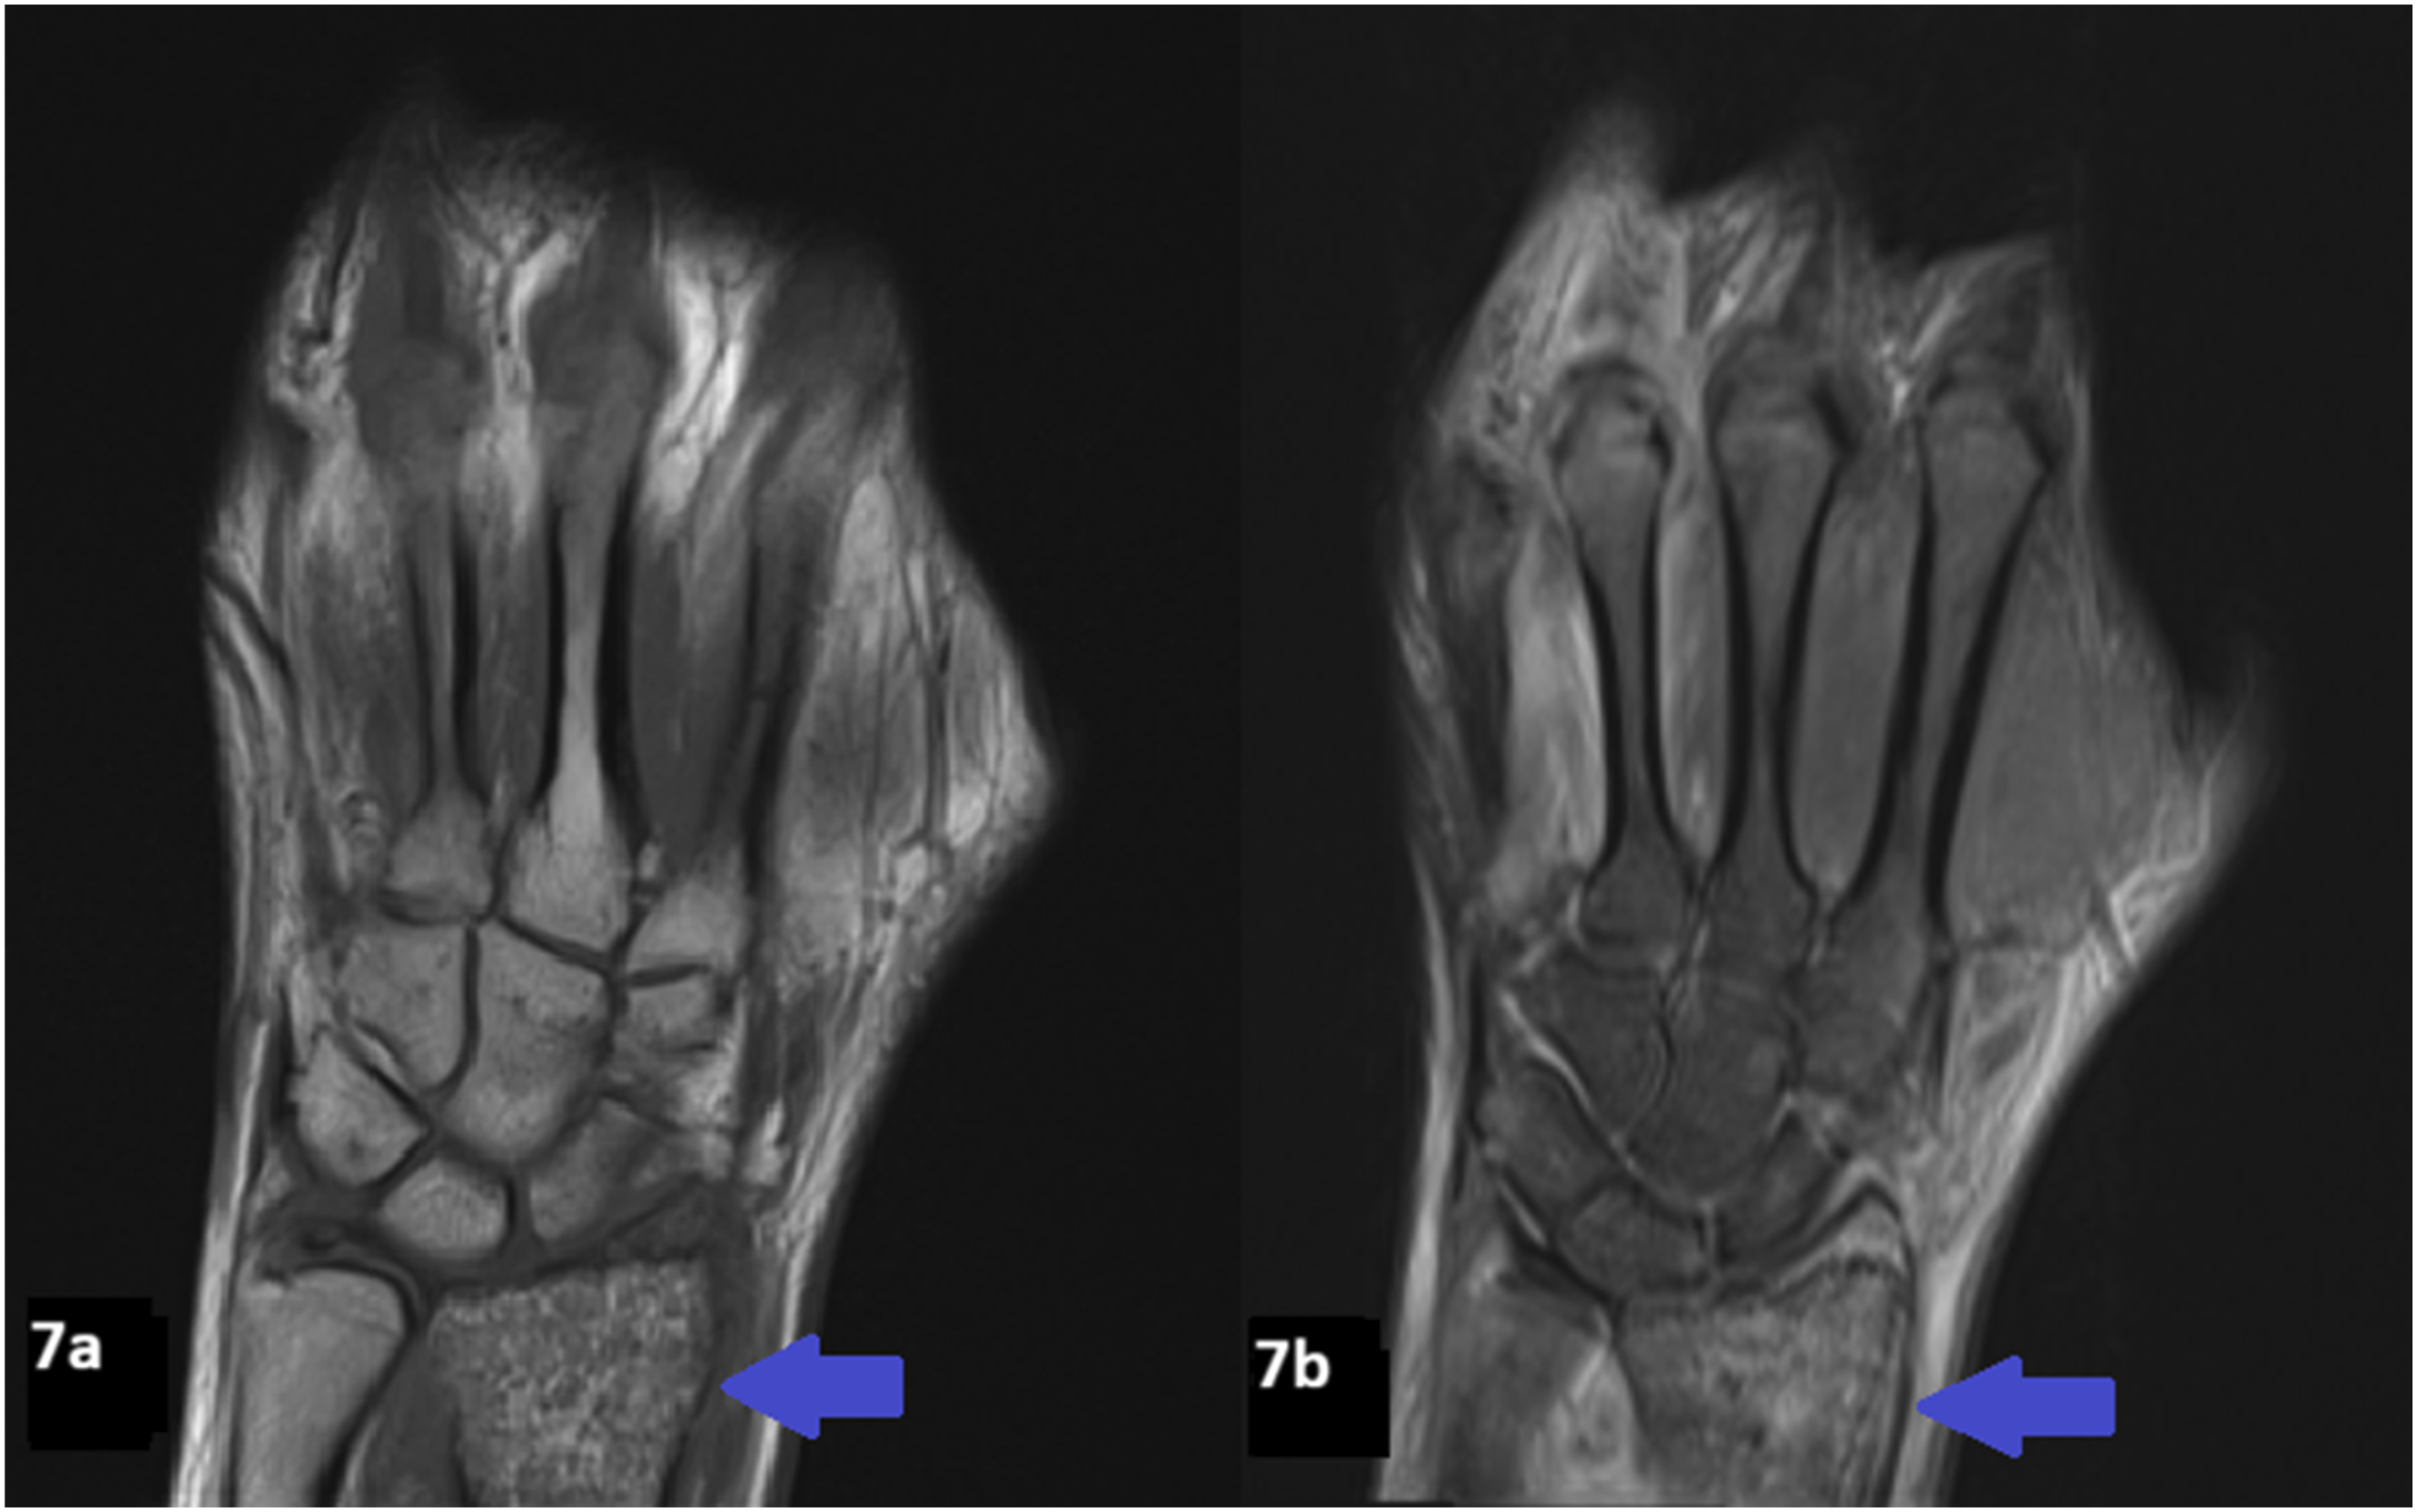

Radiographs of the hands revealed multifocal permeative lucencies involving the distal radius and multiple phalanges (Figure 5), raising concern for systemic arthropathy or osteomyelitis. MRI of the hands showed bone marrow signal abnormalities consistent with multiple bone infarcts (Figures 6–8). Radiographs of the hand showing permeative lytic lesions involving left distal radius and multiple phalanges (blue arrows). (a) Coronal T1W and (b) Coronal STIR MRI of the right hand reveals bone infarcts at the scaphoid and middle finger proximal phalanx. (a) Coronal T1W and (b) STIR MRI of the left hand demonstrates patchy T1 hypointense signal and STIR hyperintense signal abnormality at the distal radius representing ischemic changes. (a) Coronal T1W, (b) Coronal STIR, (c) Axial STIR, and (d) Post contrast T1FS of the left hand demonstrates bone infarct at the ring finger proximal phalanx, and soft tissue edema and enhancement.